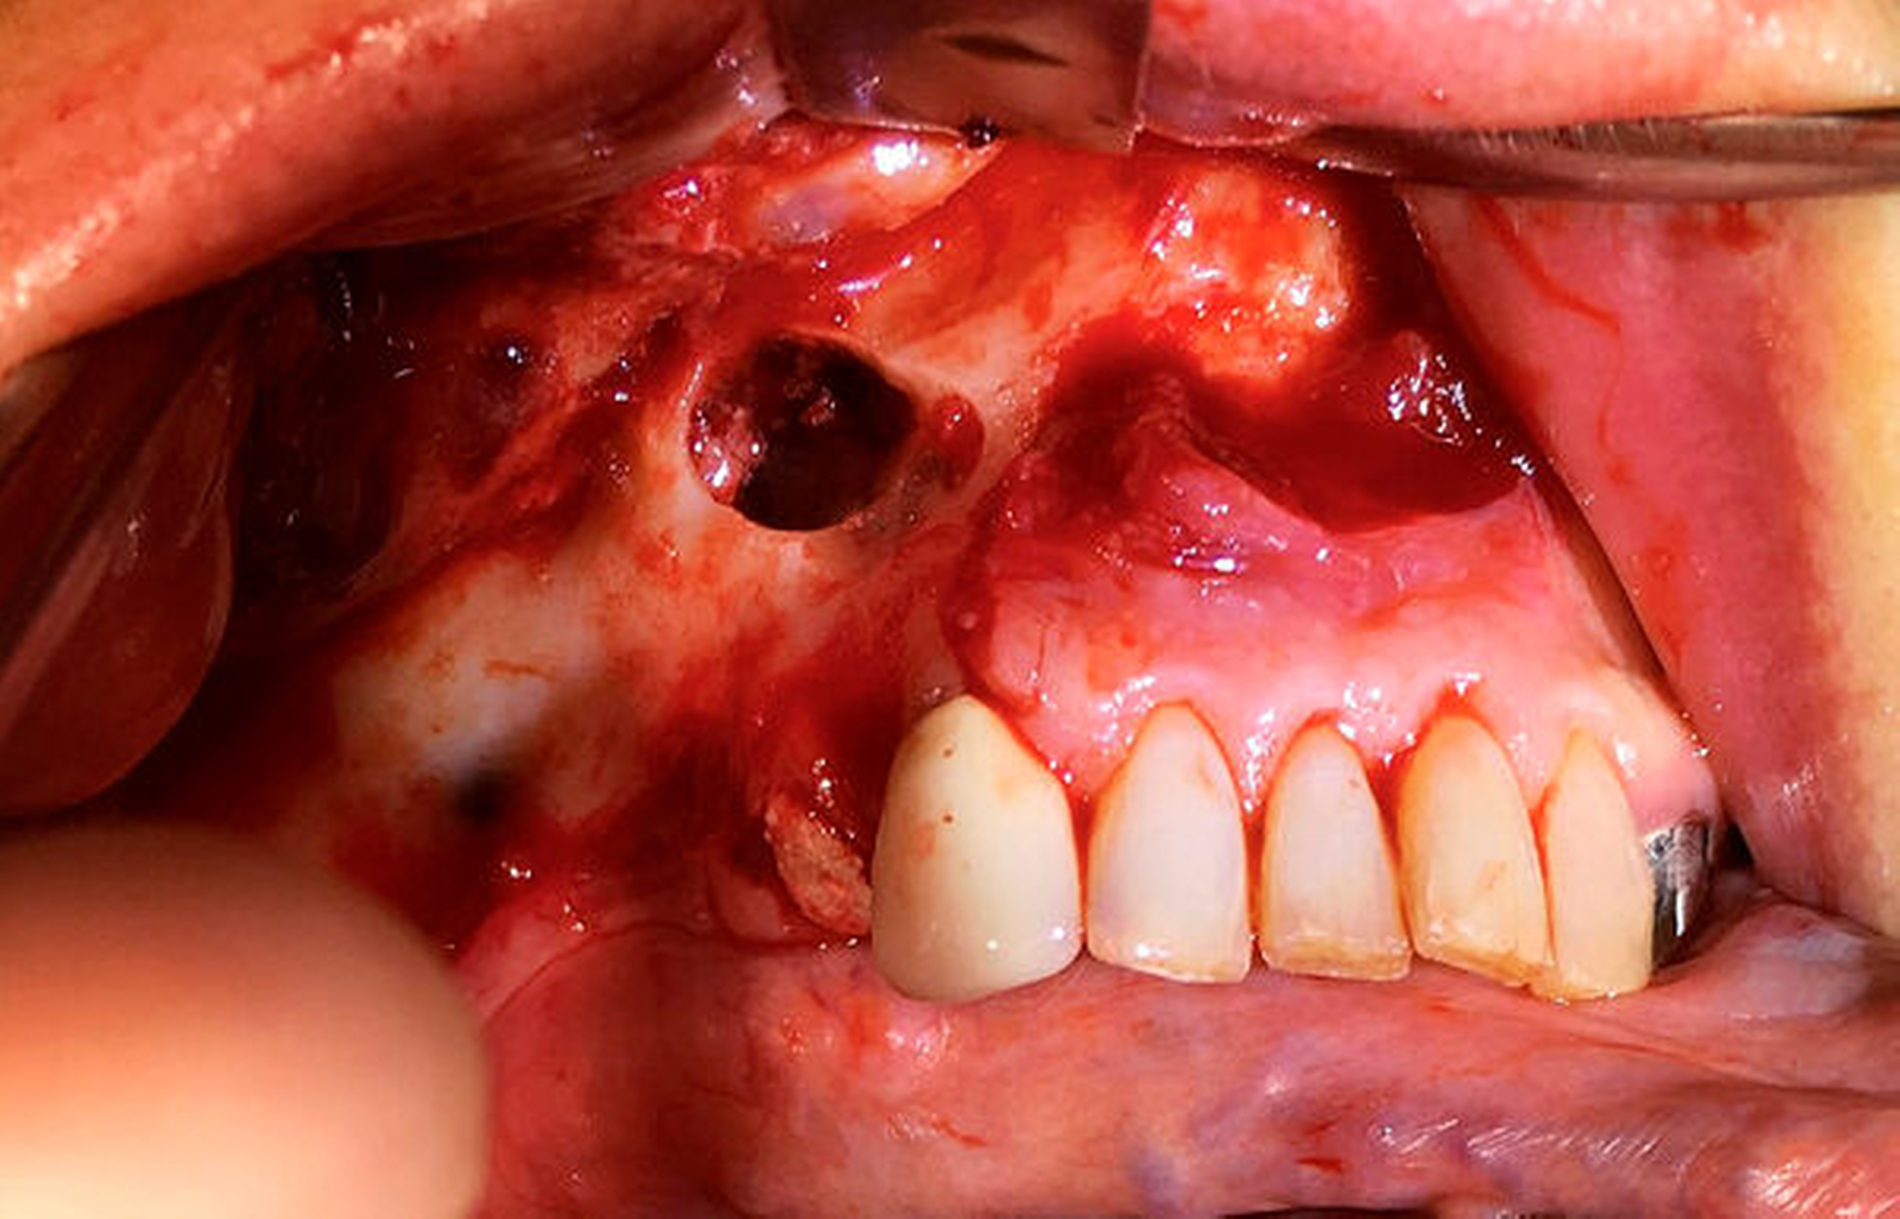

Der intraoperative Situs zeigte nach Abklappen des Mukoperiosts die Zugangskavität der alio loco durchgeführten Wurzelspitzenresektion. Der Wurzelrest 44 ist hierbei noch in situ (Abbildung 5).